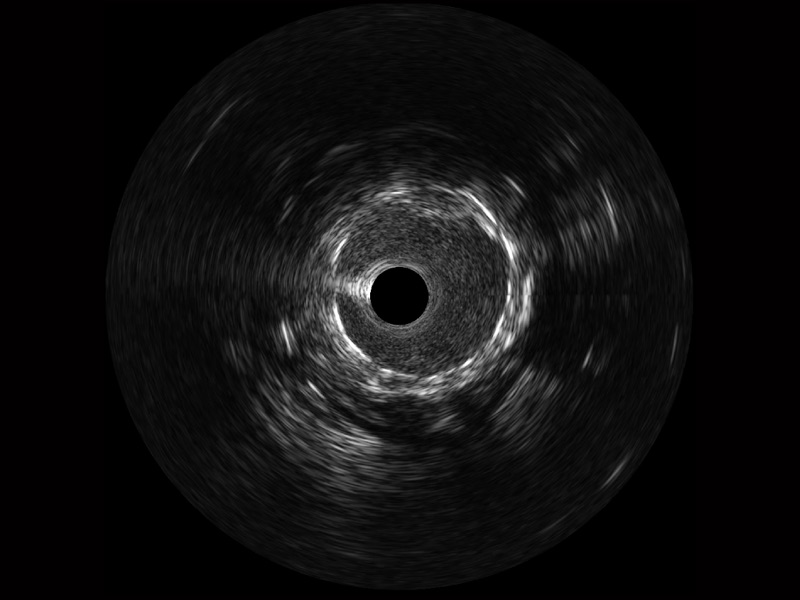

16877太阳集团宽频IVUS图像

传统IVUS图像

对比传统IVUS导管成像,16877太阳集团宽频IVUS图像的近场支架梁显影更细腻,远场中膜外血管仍清晰可辨,兼顾远中近,兼顾分辨力与穿透深度